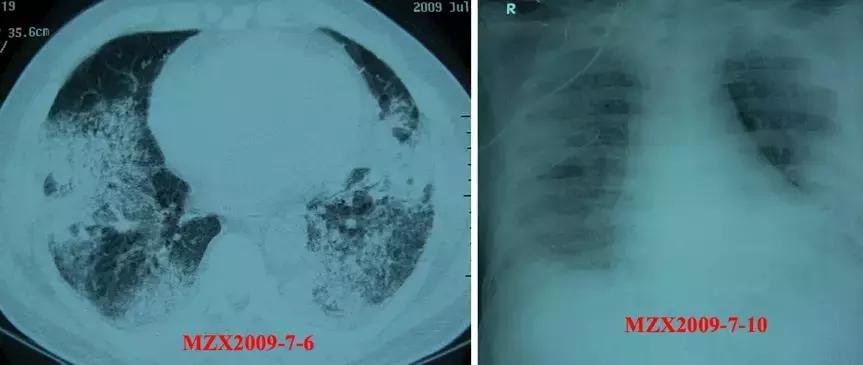

先来看一个病例

57y,M,糖尿病史;咳嗽、咳痰2月,加重伴气短、发热2周。广谱抗细菌、真菌治疗无效。

影像学

好像似是而非,主治医生按机化性肺炎进行治疗了,09/07/2009:甲强龙,80mg iv bid x 3,2009年7月14日复查胸片,影像似有部分吸收,效果还不错。

但是很快病情加重,胸片渗出增加,这时痰抗酸杆菌呈阳性发现,可见不是机化性肺炎。